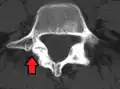

(A) CT sagittal view of a low grade slip.

(B) Lateral radiograph pre-operative intervention.

(C) Surgically treated with L5–S1 decompression, instrumented fusion and placement of an interbody graft between L5 and S1.